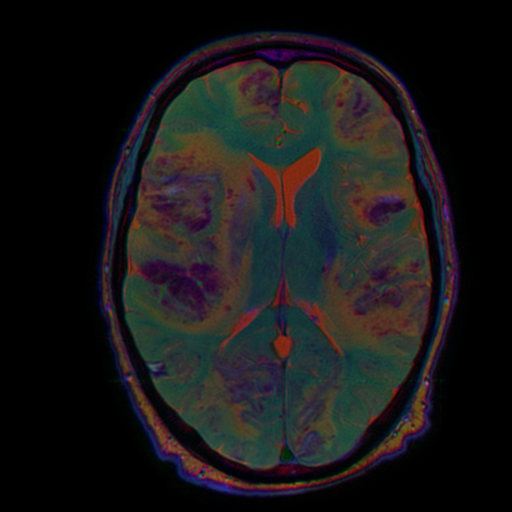

Каждая из этих серий содержит полезную информацию, и мы хотим показывать нейросетке все три взвешенности. Для этого их нужно подавать как каналы (примерно так, как делал фотографии Прокудин-Горский в начале 20 века: делал три фотографии через разные светофильтры, а потом накладывал их друг на друга).

stacked = np.stack([t2_sitk_array, swi_resampled_array, t1_resampled_array,])

to_rgb = stacked[:,t2_sitk_array.shape[0]//2,:,:].transpose(1,2,0)

im = Image.fromarray((to_rgb * 255).astype(np.uint8))

im

final